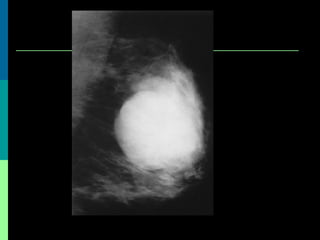

• #19 Imaging Studies Although mammography and ultrasonography generally are important in the diagnosis of breast lesions, they are notoriously unreliable in differentiating benign cystosarcoma phyllodes (CSP) from the malignant form of the condition or from fibroadenomas. Thus, findings on imaging studies are not definitively diagnostic of CSP.6 Most frequent anomaly is regular oval margines On ultrasound the tumours were lobulated in most of the cases. Heterogeneous internal echoes and ntramural cysts are also said to be suggestive of phyllodes tumours5. Phyllodes tumour on mammography is described as a sharply defined round or oval mass with lobulation5

• #20 reported mammo-graphic and sonographic findings between benign and malignant phyllodes tumors. Cystic areas at sonography were more common in malignant than benign tumors. These data suggested that a malignant phyllodes tumor was likely to undergo cystic formation. There is possible malignancy in phyllodes tumors showing intracystic growth.

• #21 reported mammo-graphic and sonographic findings between benign and malignant phyllodes tumors. Cystic areas at sonography were more common in malignant than benign tumors. These data suggested that a malignant phyllodes tumor was likely to undergo cystic formation. There is possible malignancy in phyllodes tumors showing intracystic growth.